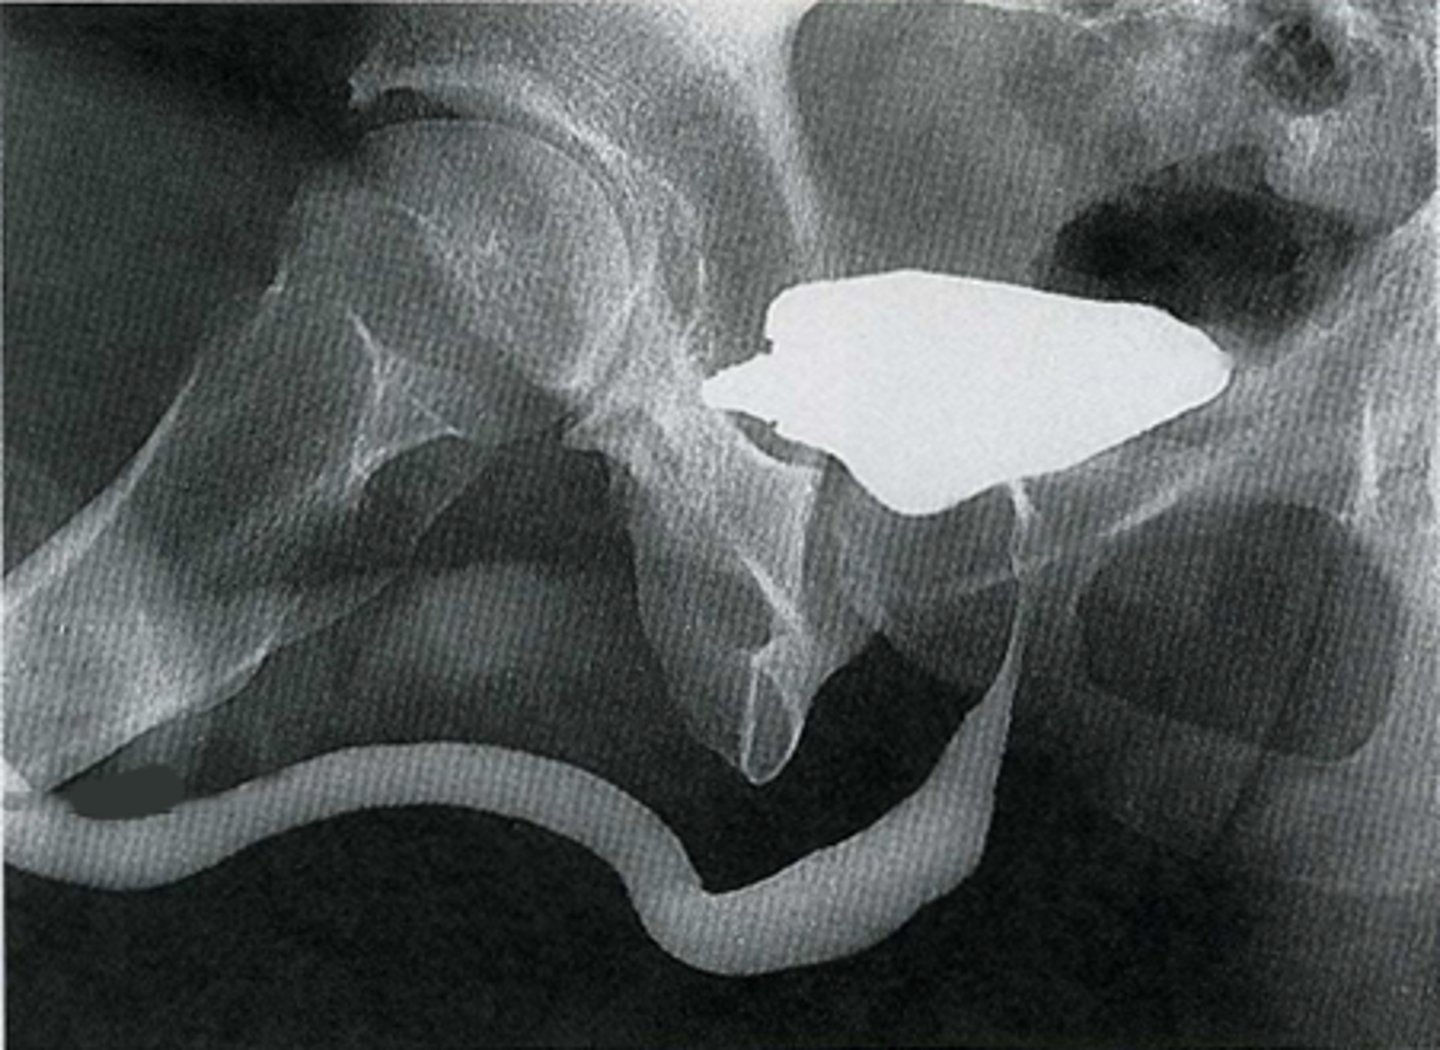

5

Intravenous pyelogram (IVP)

What is the image?

<p>What is the image?</p>